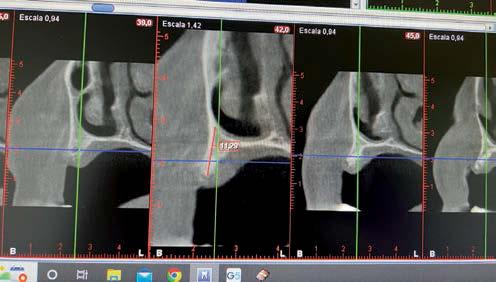

Elevación de seno transcrestal con implantes cortos versus elevación de seno convencional con ventana lateral

Estudio retrospectivo comparativo a boca partida

Aún así, existen hoy en día situaciones en las que la inserción de un implante corto o extra-corto no es posible de forma directa, cuando existe un volumen óseo residual por debajo de los 5 mm, existiendo en estos casos una nueva alternativa terapéutica a la elevación de seno convencional que es la elevación de seno transcrestal (14-15).

En esta técnica se accede a través de la cresta mediante la confección de un neoalveolo generado por fresado al seno maxilar despegándose la membrana desde este neoalveolo e insertándose el implante corto o extra-corto con o sin injerto asociado (en función del volumen en altura que se pretende ganar) (14-15).

Ya que ambas técnicas quirúrgicas siguen hoy en día en pleno auge, aunque las indicaciones para cada una de ellas han evolucionado en el tiempo, quedando la elevación convencional únicamente indicada hoy en día en aquellos casos de 1-2 mm de volumen óseo residual (donde es muy complejo estabilizar un implante corto por elevación transcrestal), creemos útil poder comparar la evolución de ambos procedimientos en el tiempo, a ser posible en un mismo paciente, donde el resto de variables que puedan afectar al seguimiento sean iguales, y, por lo tanto, la comparación sea más útil. Por ello, hemos realizado un análisis retrospectivo de pacientes en los que se han realizado los dos procedimientos, uno en cada cuadrante superior y ver la evolución en el tiempo de los implantes insertados en cada caso. Con esta idea en mente, hemos llevado a cabo un estudio retrospectivo que evaluase estos factores, y que se detallan a continuación.

MATERIAL Y MÉTODO

Fueron reclutados de forma retrospectiva pacientes en los que se hubiesen realizado ambas

técnicas de abordaje de seno maxilar: elevación convencional o la inserción de implantes cortos y extra-cortos mediante elevación transcrestal, desde enero de 2010 en adelante. Todos los pacientes fueron estudiados antes de la inserción de los implantes mediante modelos diagnósticos, exploración intraoral y realización de un TAC dental (Conebeam) analizado posteriormente mediante un software específico (BTI-Scan II).